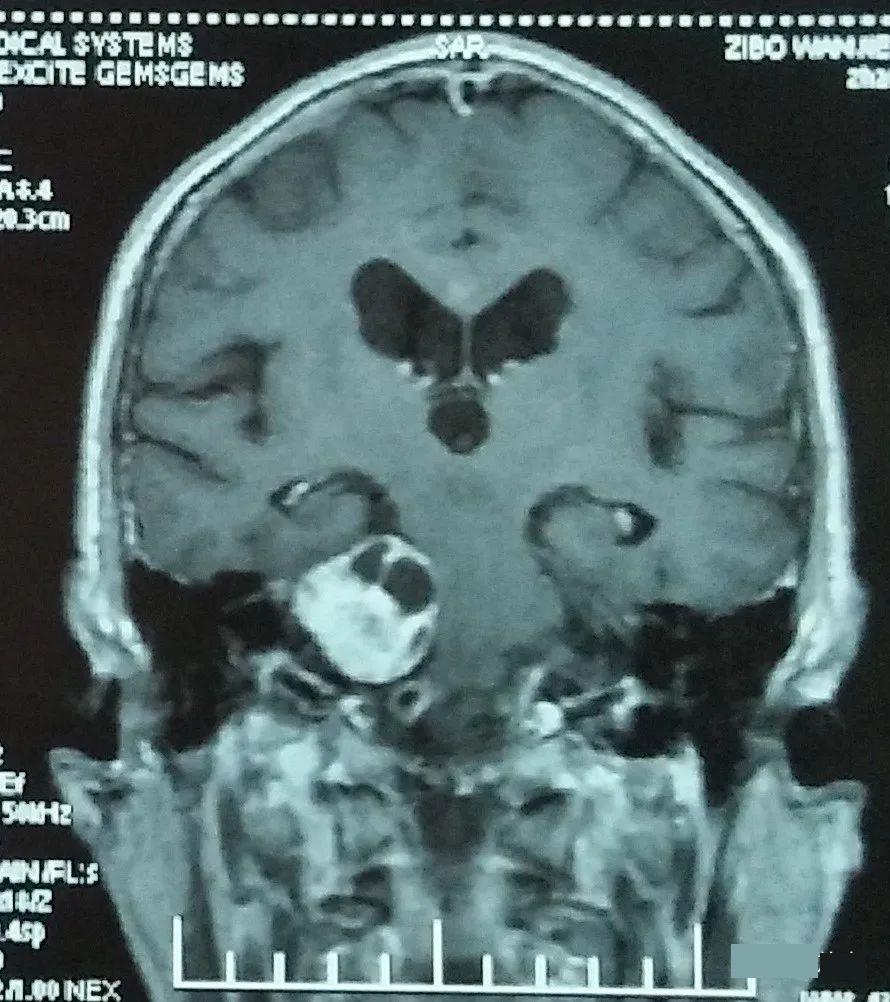

退休在家的张叔在2009年出现右耳耳鸣伴听力下降,逐渐加重至右耳完全失聪。2011年7月行颅脑MR检查,发现右侧CPA区软组织信号影,轴位最大面积约2.2*1.4cm,考虑右侧听神经瘤。2012年4月颅脑MR示病灶增大到2.5*1.5cm,脑干受压。因为病灶未明显影响到生活质量,略有些固执的张叔不愿积极处理。直到2015年9月出现右侧面部感觉麻木、头晕、走路不稳,复查颅脑MR时,病灶进一步增大约3.0*3.5cm,内听道明显扩大,脑干及四脑室受压变形。

届时张叔年事已高,不愿接受手术,2015年11月选择质子放射治疗:2.0CGE×27次,治疗结束后复查,病灶就略有缩小。后定期复查颅脑MR示右侧CPA区病灶逐渐缩小,张叔头晕、面部麻木等症状均得以缓解。随访时已76岁的张叔精神特别好,还跟年轻朋友们打乒乓球呢!

现质子治疗已5年,复查颅脑MR,右侧听神经瘤已几近消失!